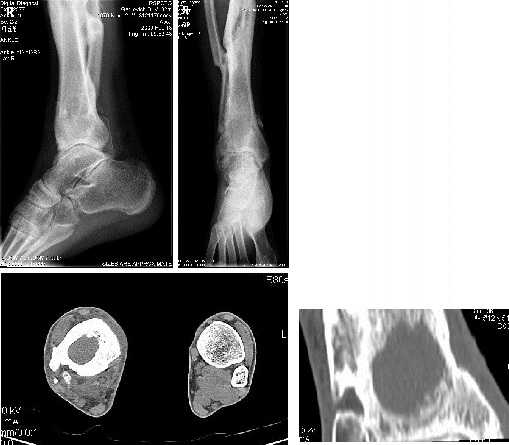

У пациента 31 года после ВКДО голени по Илизарову хронический остеомиелит дистального отела большеберцовой кости.

Пацент лечится у нас с 2005 года когда по поводу несращения с/3 голени был применен ВКДО по Илизарову. Достигнута консолидация, аппарат демонтирован. Через 2 года после снятия аппарата появился свищ над внутренней лодыжкой. Осенью 2007 года - ФНЭ, аутопластика дефекта метафиза аутоспонгиозой из проксимального отдела большеберцовой кости - в течение года ремиссия.В ноябре-декабре 2008 вновь открылся свищ, произведена хирургическая обработка, в настоящее время скудное серозное отделяемое. Конечность полностью опорна, болей нет.Вопрос: чем лучше заполнить дефект метафиза: губкой из крыла подвздошной кости или каким-либо заменителем (хотя инфицирование остается)?Спасибо,Александр Ситник